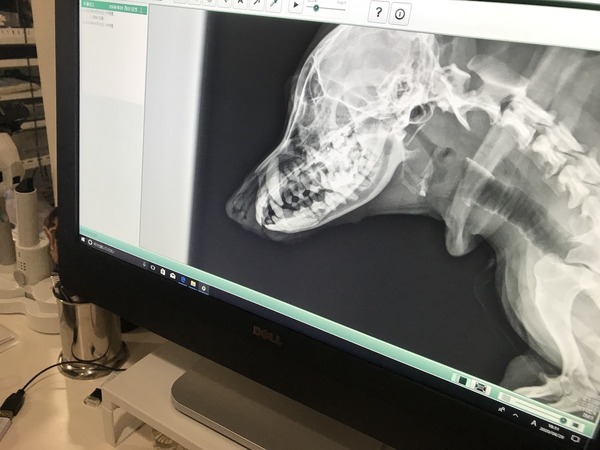

昨夜のロコはアタシのベッドで痛みに耐えてました。多分今夜が1番辛いはず。とりあえずずっと撫でる。今朝はずっとメル婆が寄り添ってます。メンテナンスしてあげてます。くっついて離れない母。すっかり元気になりましたよ。ポチっとよろしくお願い致します。メルロコのお洋